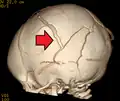

A skull fracture from abusive head trauma in an infant -

3D CT reconstruction showing a skull fracture in an infant -

3D CT reconstruction showing a skull fracture in an infant